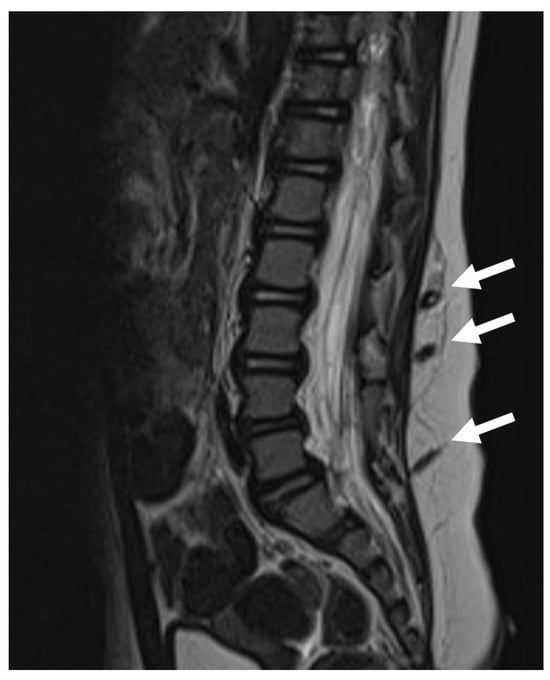

In 13/52 (25%) cases there were two different dysraphic lesions. Two patients had three different dysraphic lesions (Figure 1). In total, there were 64 dysraphic lesions (Table 1): 22/64 (34.3%) conus lipomas (transitional in 13/22 (59%) cases, dorsal in 7/22 (31.8%) cases and chaotic in 2/22 (9%) cases); 13/64 (20.3%) dermal tracts; 12/64 (18.7%) LFTs; 5/64 (7.8%) SCMs; 3/64 (4.6%) agenesis of the conus as part of caudal regression syndrome; 2/64 (3.1%) LDM; 2/64 (3.1%) dermoid cysts; 2/64 (3.1%) presacral meningoceles as part of Currarino syndrome; 1/64 (1.5%) neurenteric cyst; 1/64 (1.5%) epithelialized MMC; and 1/64 (1.5%) meningocele.

Figure 1. MR scan of a paediatric patient with three concomitant dermal tracts (white arrows). The conus is located at a physiological level L1.